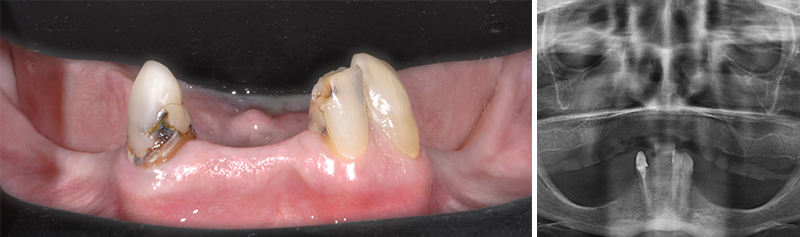

Fig. 36 et 37 : présentation du second cas.

Étude préimplantaire :

L’arcade maxillaire traitée en premier a bénéficié d’un protocole DSD. La mandibule n’a d’autres challenges que de s’adapter au maxillaire idéalement reconstruit et d’offrir un sourire régulier souhaité par la patiente.

Une empreinte numérique avec la caméra VirtuoVivo (Dentals Wings) est réalisée et l’étude préimplantaire sera réalisée simultanément à la planification.